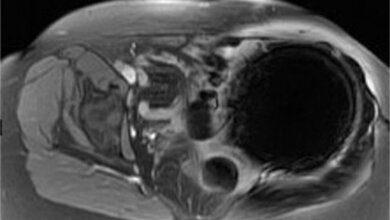

MRT eines Gehirns © sudok1 - Fotolia

Ein einfacher Hirn-Scan kann Hinweise darauf liefern, ob ein frühgeborener Säugling geistige oder Bewegungsstörungen entwickeln könnte. Zu diesem Schluss kam eine kürzlich veröffentlichte kanadische Studie.

MRT zeigt Schäden in der weißen Gehirnmasse

Doch wie ein kanadisches Team nun herausfand, kann ein MRT hier wichtige Hinweise auf mögliche Entwicklungsschwierigkeiten geben. Das kanadische Team untersuchte in einem Zeitraum von sieben Jahren 58 Frühchen, die im British Columbia's Women Hospital mit Verletzungen in der weißen Gehirnsubstanz zur Welt kamen. Das Ziel der Studie war es, mit Hilfe der Magnetresonanztomographie (MRT) Schäden in der weißen Gehirnmasse quantitativ zu ermitteln und das Ausmaß und die Lokalisation der Schäden in Verbindung zu setzen mit den Entwicklungstadien der Frühchen bei 18 Monaten. Die Lage der Verletzungen wurde zunächst in der 32. Woche nach der Geburt ermittelt und die Kinder wurden erneut im Alter von 18 Monaten auf ihre geistigen und motorischen Fähigkeiten untersucht.

Die Ergebnisse dieser Untersuchungen zeigten, dass die Position der Verletzung Auskunft über Art und Ausmaß der Entwicklungsstörung geben kann. Lag der Schaden hauptsächlich im Stirnlappen des Gehirns, stieg das Risiko auf geistige Entwicklungsrückstande um den Faktor 79. Das Risiko auf Bewegungsstörungen wurde um das 64-fache vergrößert.

Wichtiger Einsatz bildgebender Maßnahmen

Die Deutsche Gesellschaft für Klinische Neurophysiologie und Funktionelle Bildgebung (DGKN) begrüßt den Einsatz bildgebender Verfahren, um die Gehirne von Frühgeborenen zu beurteilen. Mögliche Entwicklungsstörungen können so nicht nur früh erkannt, sondern auch gegebenenfalls behandelt werden. „Das MRT eignet sich hervorragend, um die Gehirne von Frühgeborenen auf Schäden zu untersuchen", erklärt Prof. Dr. Stefan Knecht, Chefarzt der Klinik für Neurologie der St. Mauritius Therapieklinik in Meerbusch. Während Röntgenstrahlen für Neugeborene schädlich sein können, sind die bildgebenden Magnetwellen eine harmlose Maßnahme. Hinzu kommt, dass das MRT wesentlich genauere Bilder liefert als es beispielsweise ein Ultraschall könnte. „Um auch die Langzeitfolgen der Schäden ausmachen zu können, müsste die Entwicklung der Frühgeborenen auch an weiteren Zeitpunkten während der frühen und späteren Kindheit beurteilt werden", ergänzt Knecht.